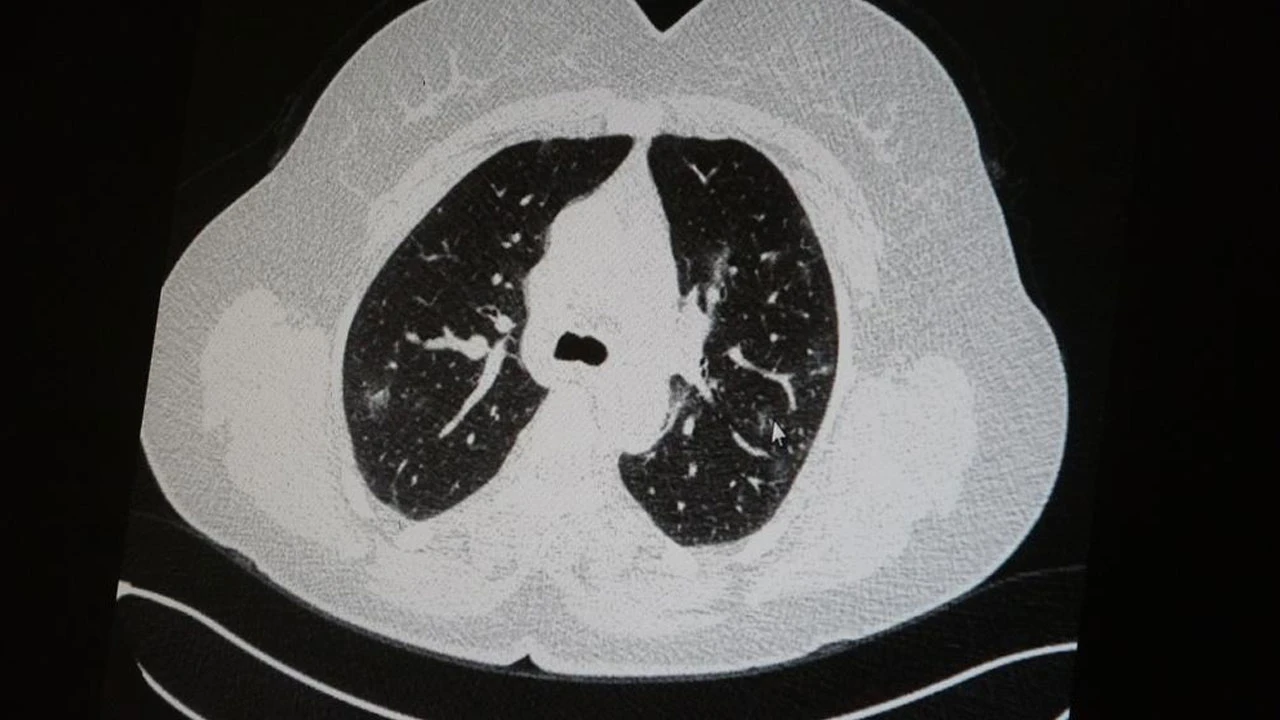

Uzm. Dr. Azar, aynı şekilde aşı olup korona virüs hastalığına yakalanan bir başka genç hastanın akciğer tomografisinde akciğerde herhangi bir sorunun olmadığını ve hastanın durumunun iyi olduğunu gözlemlediklerini kaydetti. Uzm. Dr. Azar, sürekli şahit oldukları "Keşke biz aşı olsaydık" sözünü bir daha duymamak için herkesi aşı olmaya davet etti.

Virüsle mücadele etmede en büyük silahın aşı olduğuna dikkat çeken Medical Park Elazığ Hastanesi Göğüs Hastalıkları Uzmanı Dr. Cebrail Azar, "Pandeminin önünün kesilmesi, hastaların azalması için mutlaka dikkat etmemiz gereken en önemli nokta aşı olmaktır. Özellikle ebeveynlere en büyük tavsiyemiz, aşı olmalarıdır. Son zamanlarda hastanelerde yatan hastaların büyük çoğunluğu aşısızlardan oluşmaktadır. Hastalığa yakalananların yaklaşık yüzde 80-90'ı aşısız olanlardır. Şu an yoğun bakımda yatan hastalarının çoğunun aşısız olduğunu görüyoruz. Maalesef, geçen yıl 65 yaş ve üstünde olan hasta yoğunluğu şuan 15 ile 45 yaş aralığına düşmüştür. Bu da gösteriyor ki aşı koruyor ve hastalığın ağır geçmesini engelliyor" ifadelerini kullandı.

Yakınlarında ve hastalarında "Keşke biz de aşı olsaydık" diyenlerin çoğunlukta olduğunu dile getiren Uzm. Dr. Azar, "Bunun dışında hastalığı atlatanların da bize ilk sordukları soru 'Hocam, aşımı en yakın ne zaman yapacağım?' demesi oluyor. Çünkü hastalığı ciddi geçirdiği için aşının koruyuculukta büyük bir faydası olduğunu görüyor. Şu an yoğun bakımlarda, servislerde yaş ortalaması düşüyor. Tavsiyemiz, ‘Ben gencim, benim bağışıklık sistemim kuvvetli' deyip bu virüs illetine karşı savunmasız kalınmamasıdır. Dolayısıyla hastalıkla mücadelede vücudun direnci eğer genetik olarak da zayıfsa ki bunu önceden ön görmek çok zor, o zaman maalesef hastalığa bağlı kalıcı hasarlar kalabiliyor" diye konuştu.